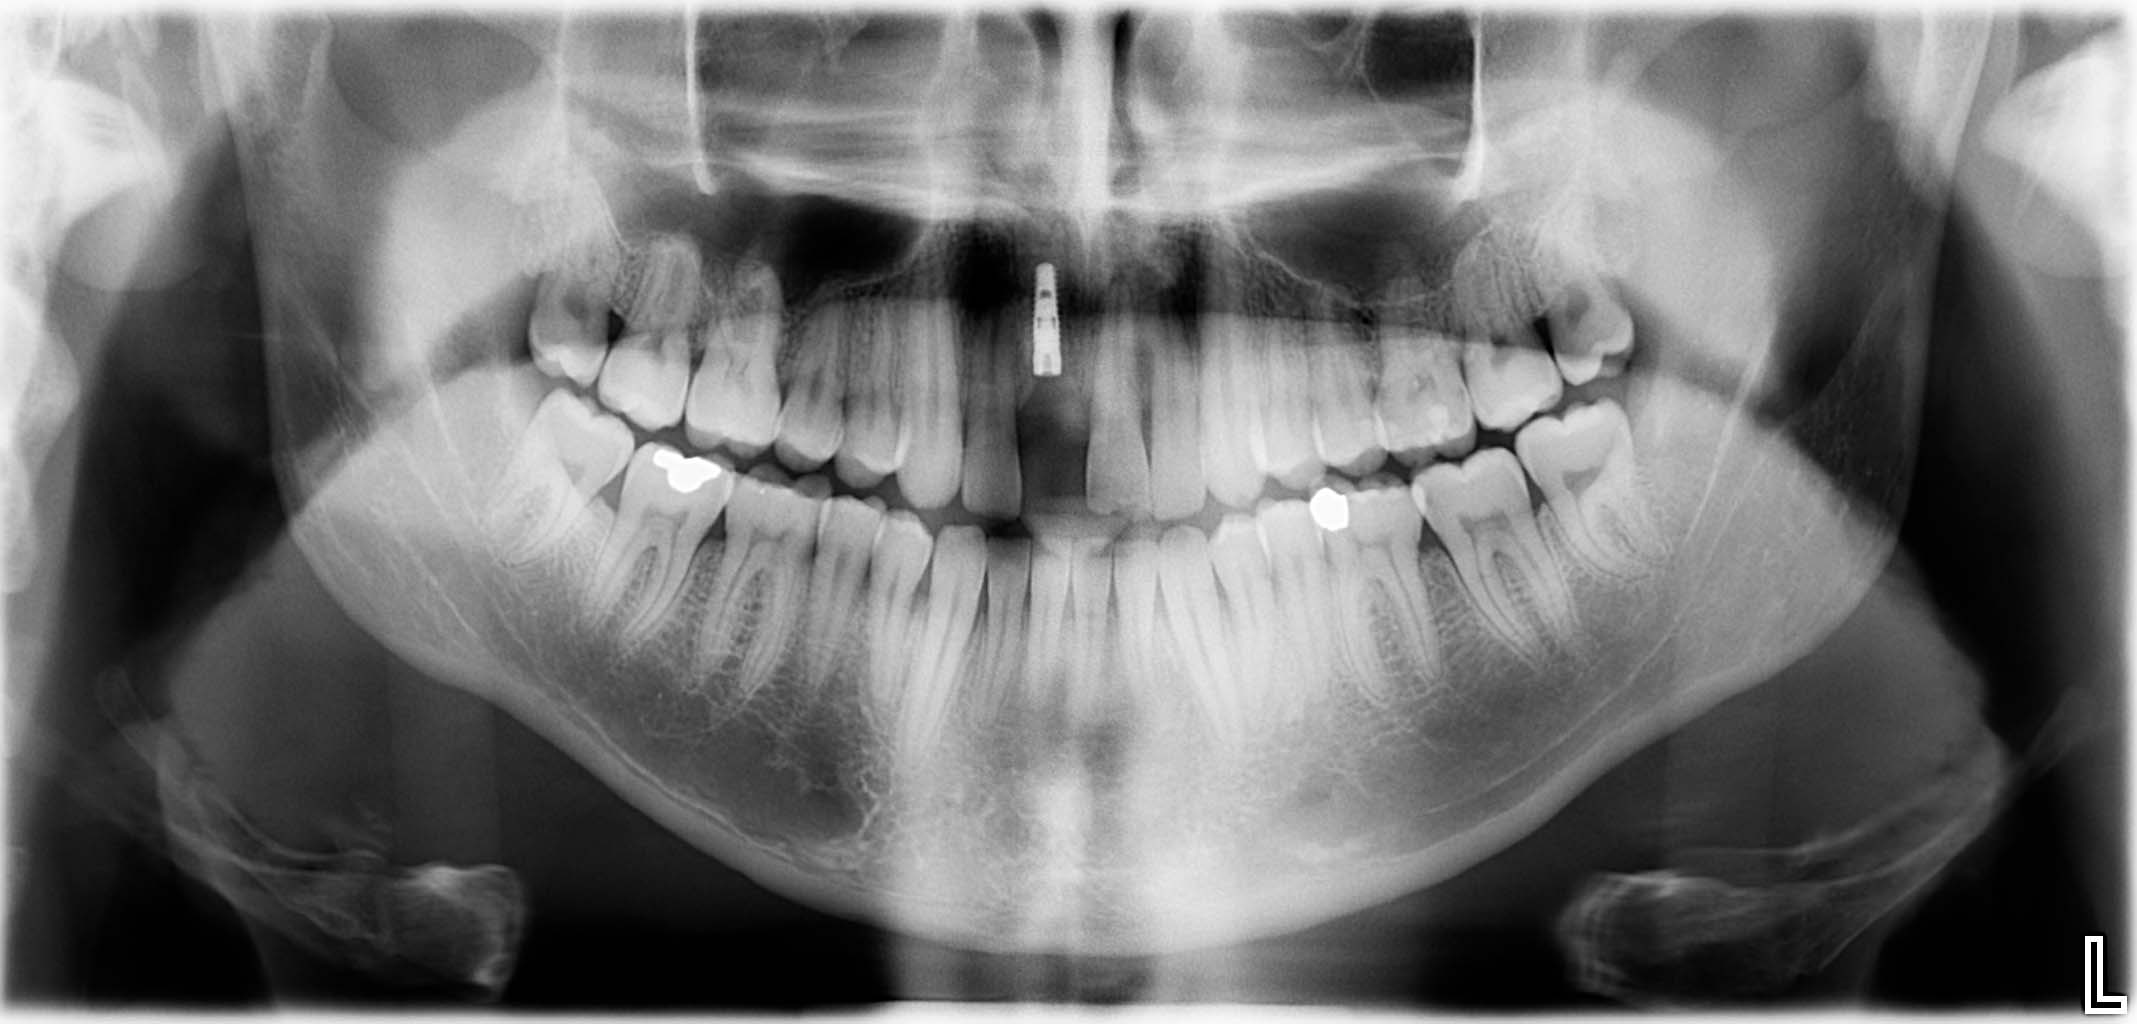

Ausgangssituation: Zahn 36 mit apikaler Beherdung, nicht erhaltungswürdig